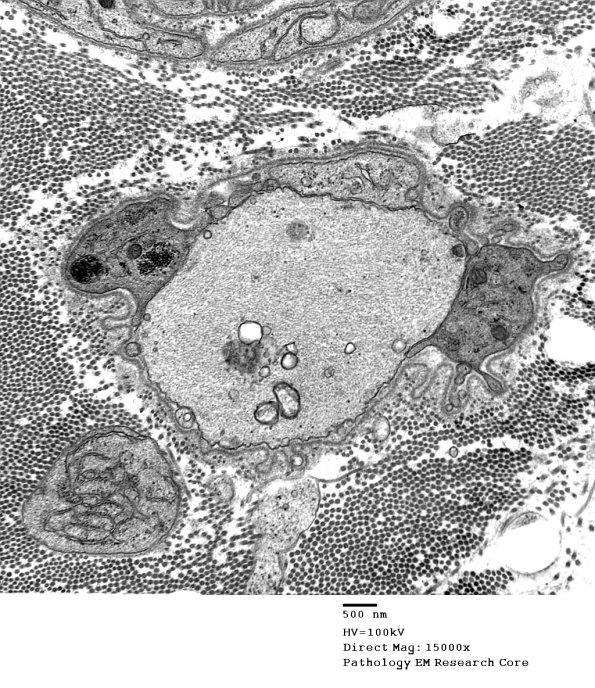

Additional demyelinated axons, some of which show redundant myelin loops. (electron micrographs)